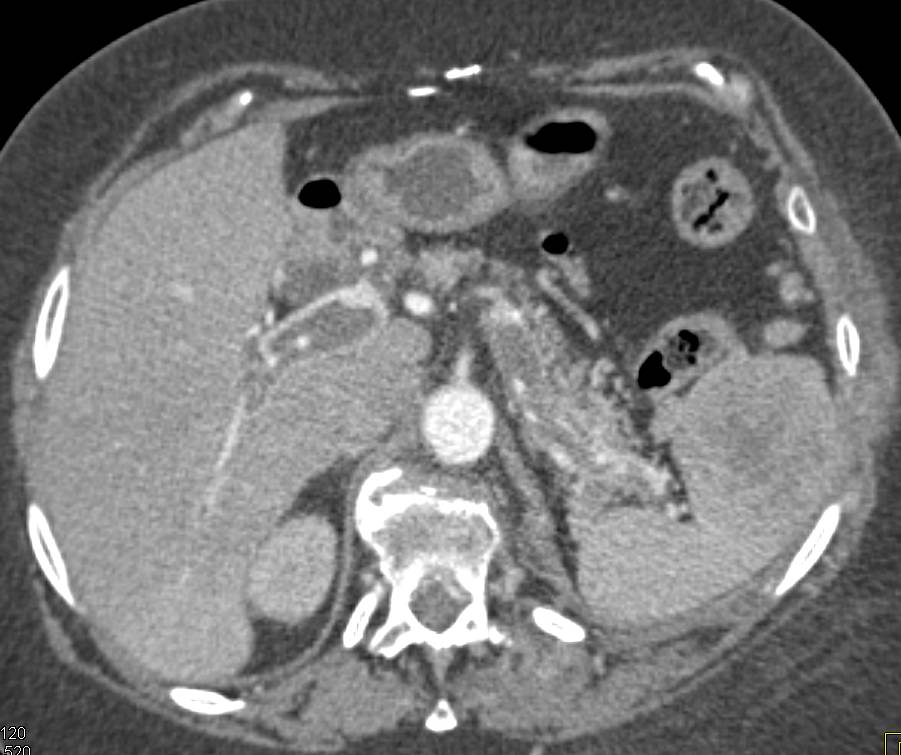

Pancreatic Cancer Infiltrates the Peri-Pancreatic Bed with Increased Enhancement of the Gallbladder